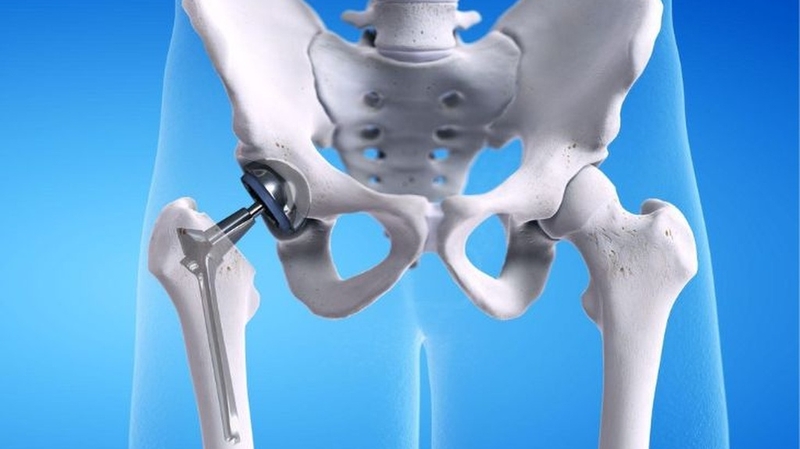

Phẫu thuật thay khớp háng được thực hiện để cắt bỏ khớp háng bị tổn thương và thay thế bằng khớp nhân tạo. Thông thường, phương pháp này chỉ được chỉ định đối với những trường hợp bị tổn thương khớp háng nghiêm trọng và không thể điều trị bảo tồn. Ở Việt Nam, kỹ thuật này đã phát triển được hơn 40 năm và đã có hàng nghìn ca bệnh được thay khớp háng thành công mỗi năm. Giúp người bệnh thoát khỏi đau và khó chịu, tái khôi phục khả năng vận động và mở ra cuộc sống mới.

Phẫu thuật thay khớp vùng háng được xem là một thành tựu to lớn trong lịch sử phát triển ngành chấn thương chỉnh hình. Kỹ thuật y khoa này thường được thực hiện ở những bệnh viện lớn với đội ngũ chuyên gia và thiết bị hiện đại, cho tỷ lệ thành công cao.